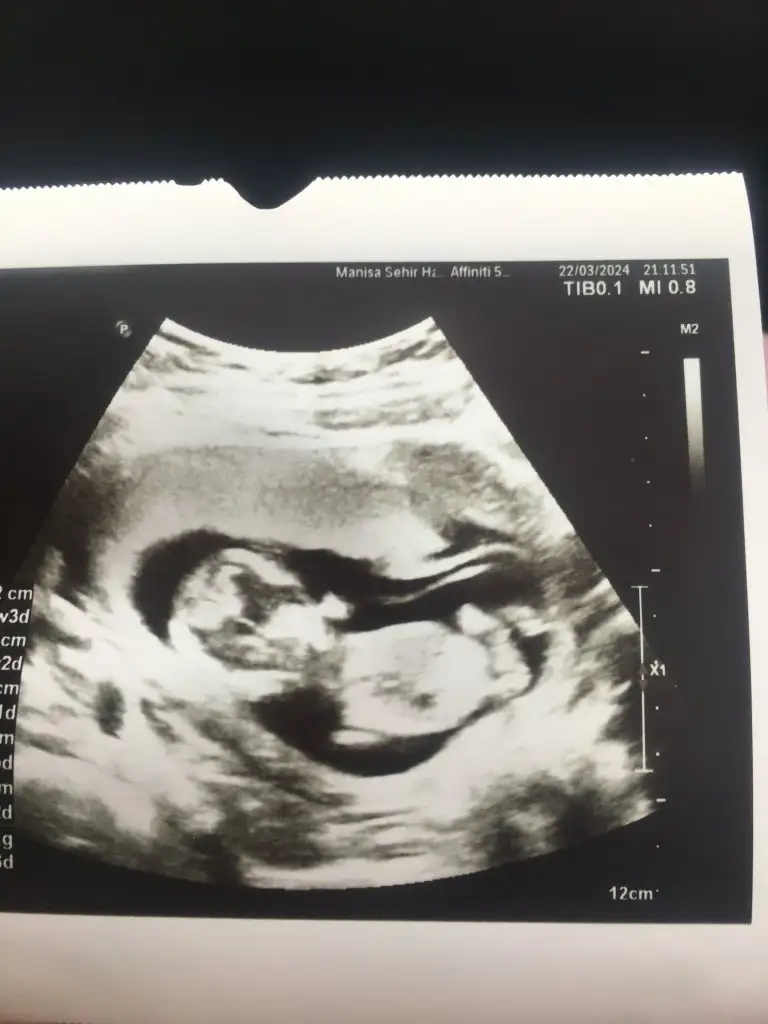

kafa ense düzse kız ama içine dogru girintili ise erkekAy nerden anladınız merak ettim valla çok teşekkür ederim bu arada![]()

Rica etsem benimkinede bakarmısınFotoya tekrar baktım bence kız bu erkek olması için çizginin yatay değil dik olmasi lazım seni ki yatay gidiyor benim kide öyleydi doktor kız dedi inşallah gönlünden geçen olur

Kiz sizinMerhabalar 10 haftalık gebeyim cinsiyet tahmini yapabilen varmı fotoğraf ekliyorum![]()

Kız benceMerhabalar 10 haftalık gebeyim cinsiyet tahmini yapabilen varmı fotoğraf ekliyorum![]()

12 haftalık tahminleri alabilir miyim kızlarBende tahmin alabilir miyim acaba

Erkek gibi canımBana da bakar mısınız 8 haftalık